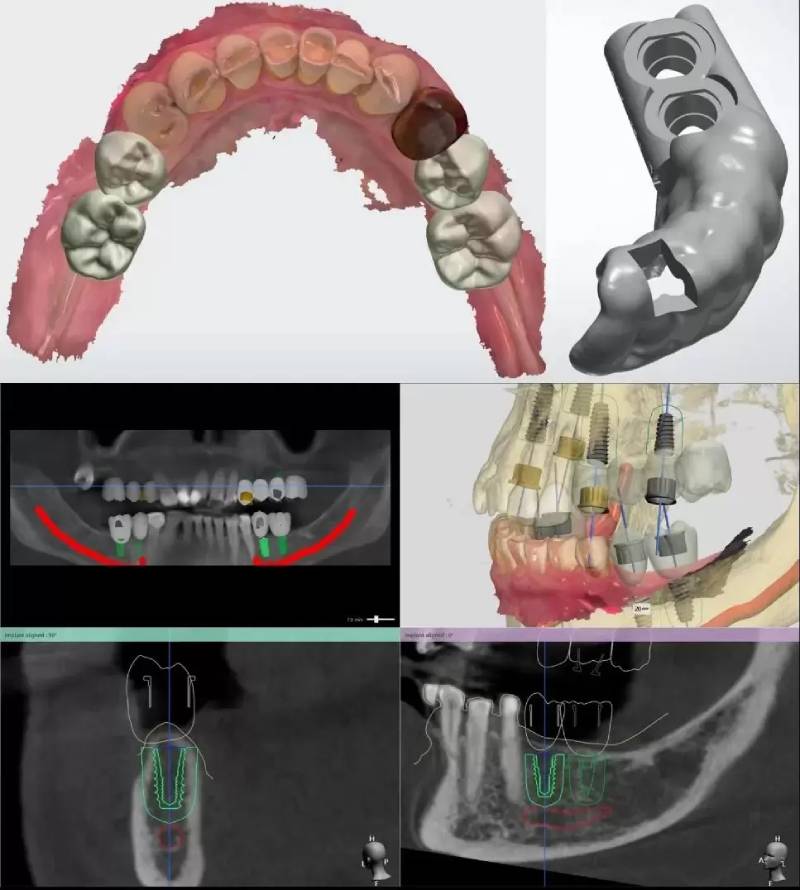

Quy trình trồng răng cửa theo phương pháp trồng răng Implant cá nhân hóa DCT gồm các kỹ thuật được tối ưu thời gian và độ chính xác dựa vào máy móc, thiết bị hiện đại như sau:

Giải pháp trồng răng Implant cá nhân hóa DCT áp dụng các máy móc hiện đại tiên tiến vào quá trình phẫu thuật